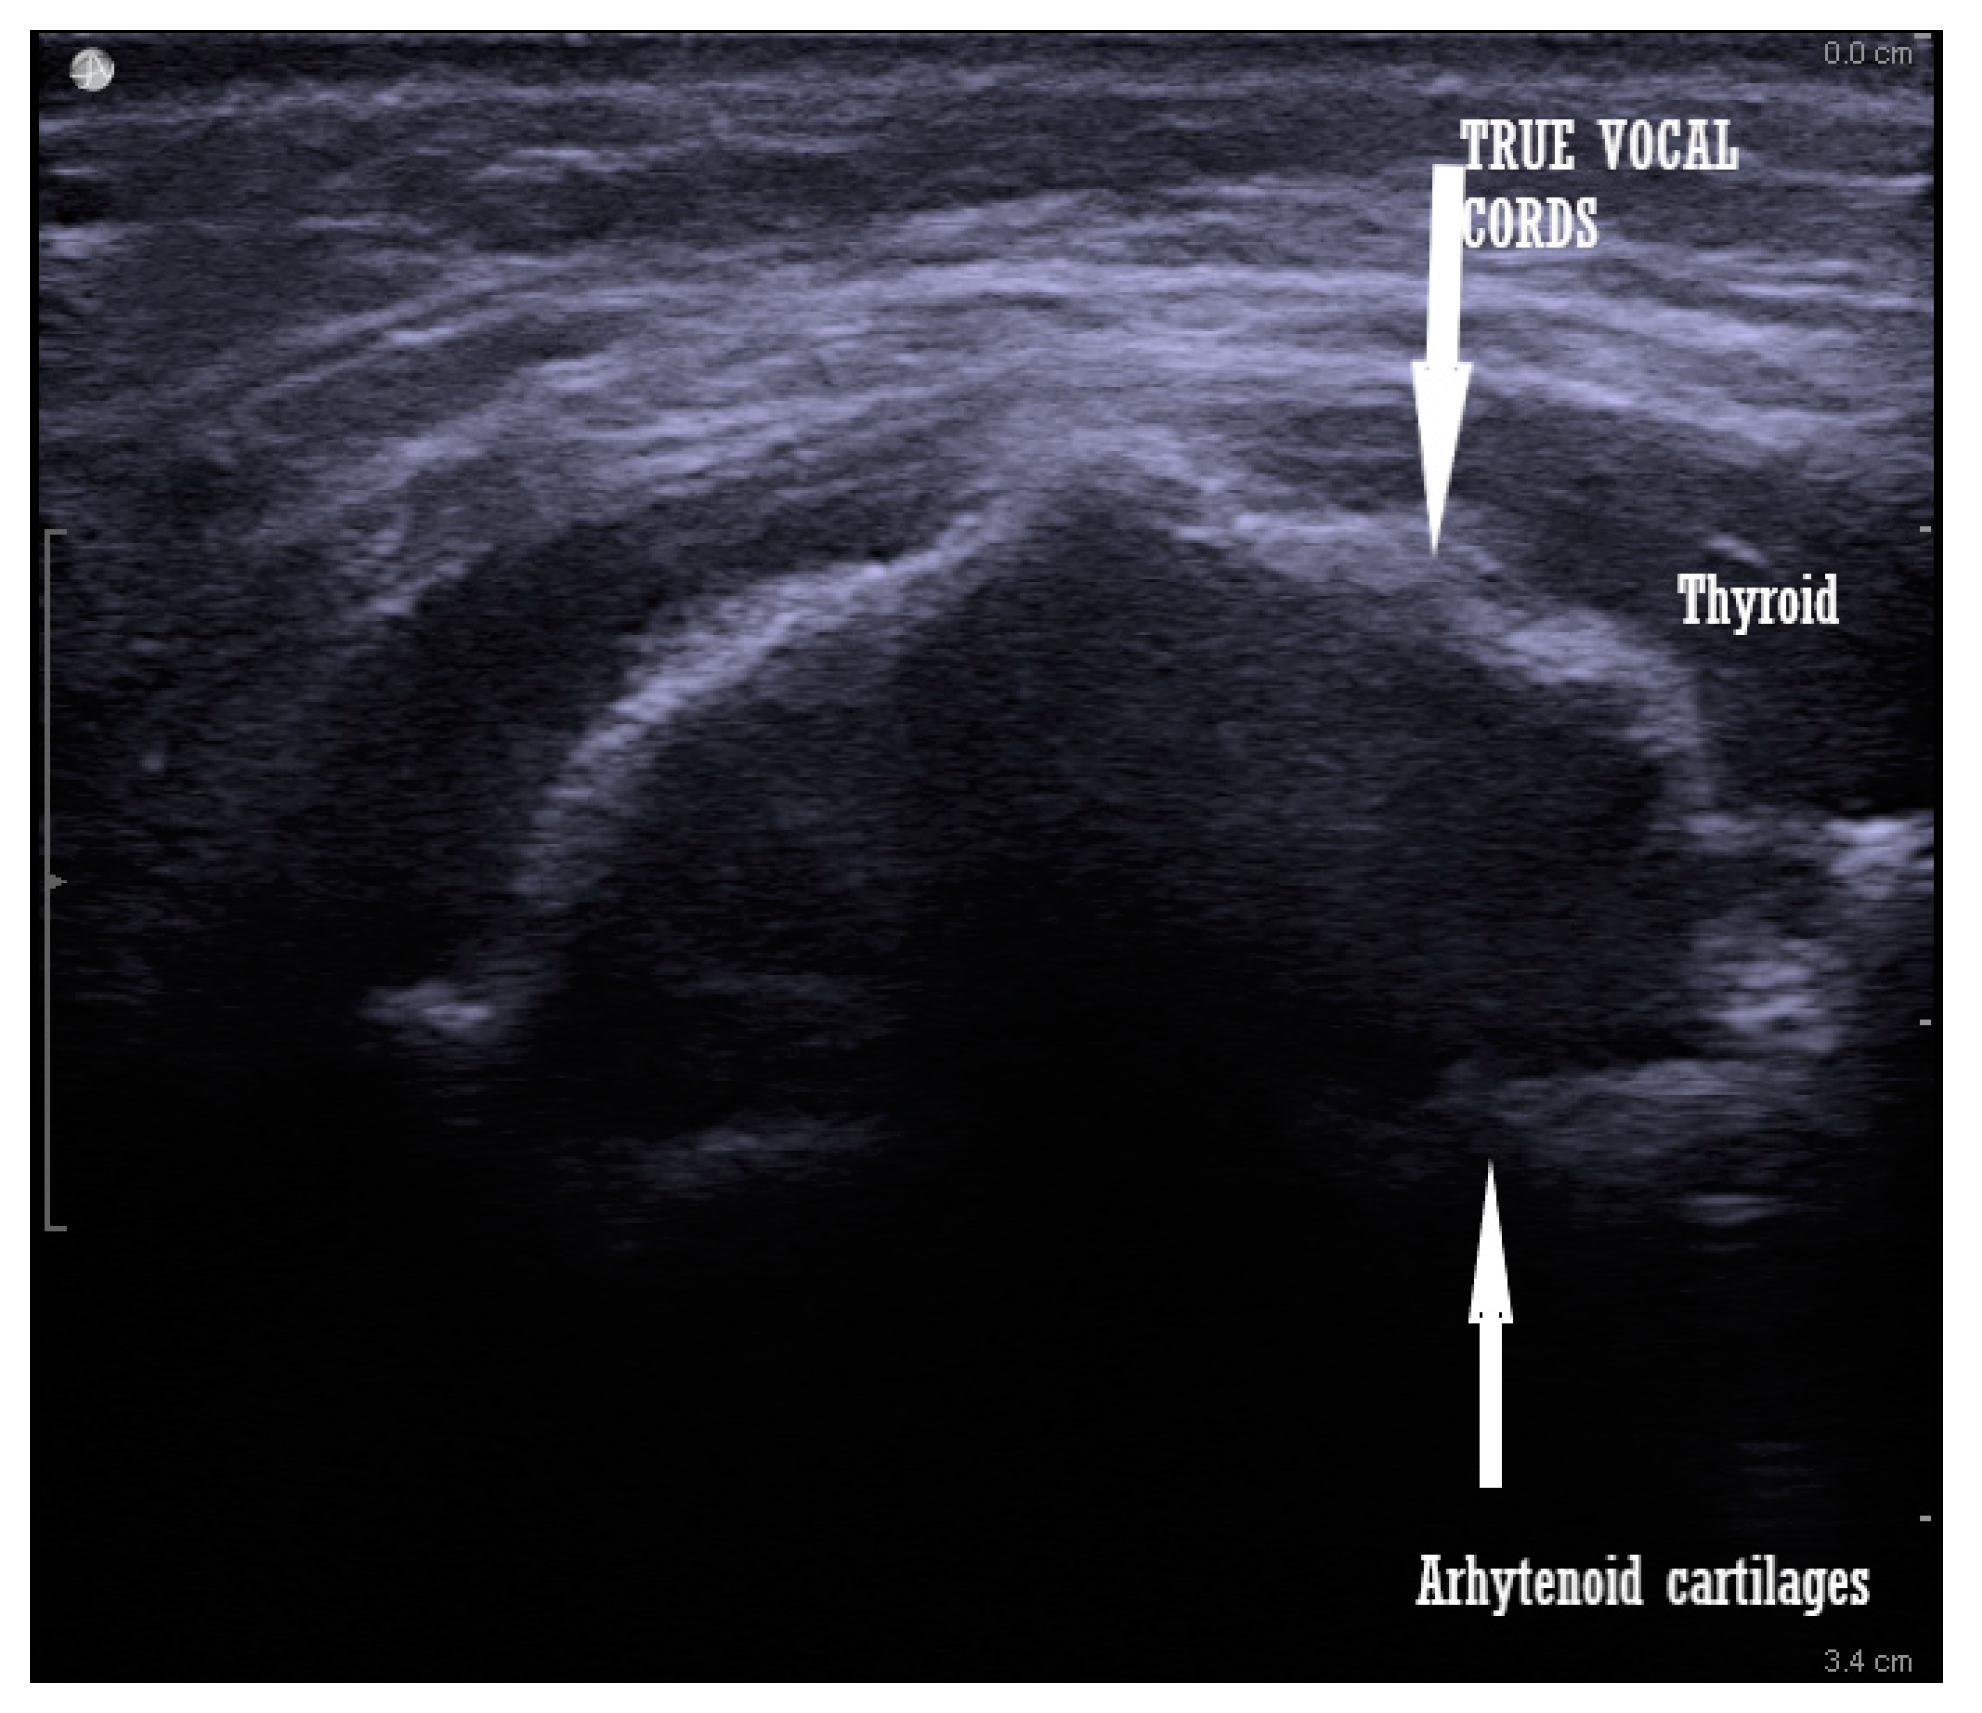

4.5. Vocal Cord Functionality

Vocal cords are visualized when the transducer is placed at the thyroid cartilage level. It can be tilted cranially or caudally for a better image. This investigation can evaluate the vocal cord mobility after thyroid surgery, after a prolonged intubation in intensive care patients, or before general anesthesia [43,44,45]. The advantages of this evaluation are that it is non-invasive, it does not cause discomfort for the patient, and it has high reproducibility, and is easy to learn and perform [46] (Scheme 2).

Scheme 2.

Vocal cord visualization in an intubated patient.